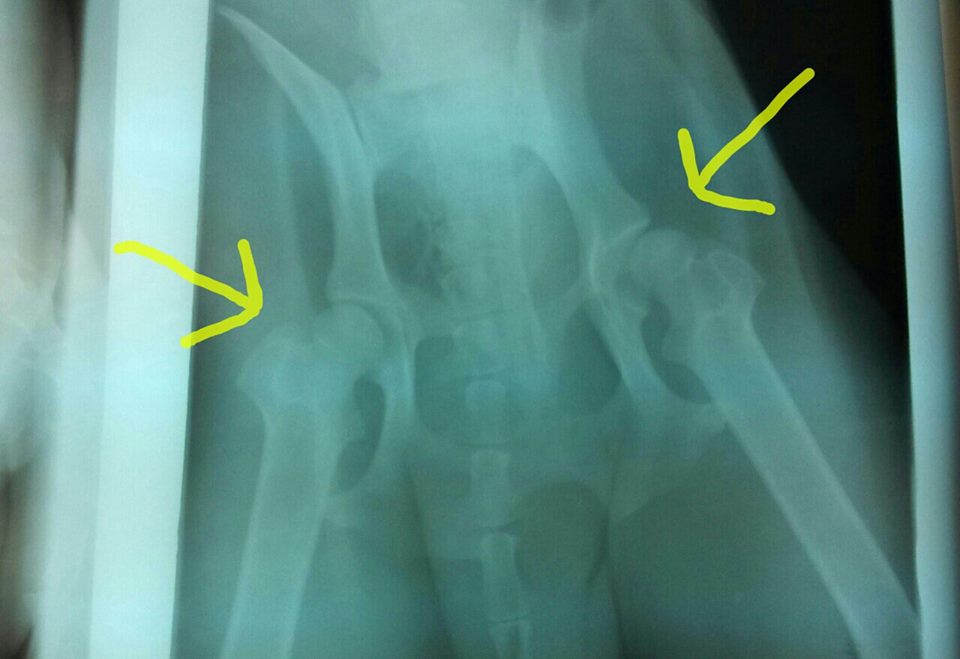

—-X-RAY UPDATE—-

Samuel had his x-rays done today (2/3/14) along with his neuter. As you can see on the right side the femoral head is sitting slightly outside of his pelvic bone (ball and socket joint). The patellas (kneecap) on both of his hind legs are also bad Ibshawāy .

The good news is that Samuel is not in any discomfort although he walks a little different than the other dogs. Also, Dr. Hedrick does not think that he needs surgery at this current time. As Samuel gets healthier he will regain his muscle mass in his hind quarters and this will hopefully help hold all of his joints in place. If it doesn’t then major surgery will be in his future. Please keep him in your thoughts.